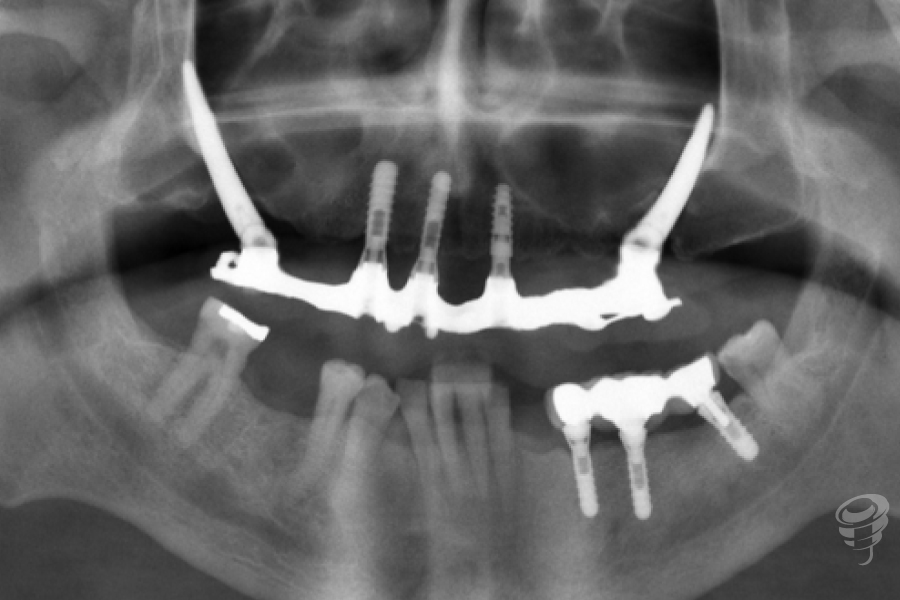

Protocolo en pacientes periodontales severos: Edentación + Implantes cigomáticos y convencionales inmediatos + Carga inmediata (CBCT y aspecto intraoperatorio de la cresta maxilar). (Imagen 14-25)

Hoy en día este protocolo nos permite abordar casos con enfermedad periodontal severa en pacientes con poco volumen óseo en sectores posteriores, que no quieren estar sin dientes, con protocolos de implantes inmediatos a extracción y carga inmediata con excelentes resultados a largo plazo. (Imagen 14-25)

Imagen 15 – Orto Preoperatoria